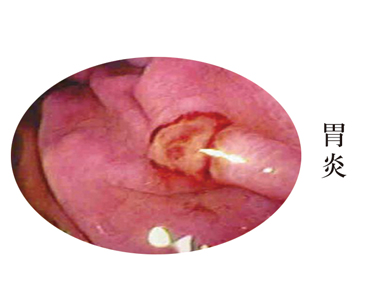

胃炎是指胃黏膜发生的炎症性或萎缩性病变。这是一种常见病,可分为急性和慢性两种类型。急性胃炎常见的为单纯性和糜烂性两种。 前者表现为上腹不适、疼痛、厌食、恶心和呕吐;后者以上消化道出血为主要表现,有呕血和黑粪。那胃炎患者需要注意哪些方面?